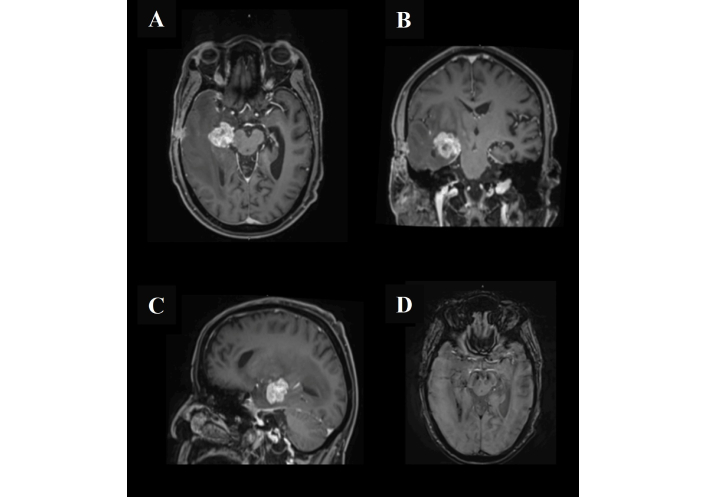

The patient underwent an initial stereotactic biopsy in November 2024 (Figure 2 is the post-operative MRI). A second biopsy was performed in December 2024 (Figure 3 is the post-operative MRI); however, both procedures were inconclusive, with histopathology demonstrating atypical lymphocytic proliferation with extensive necrosis. The first biopsy was (CD45+), and the second one immunohistochemical stains showed a positive cluster of differentiation 20 (CD20), paired box gene 5 (PAX-5), B-cell lymphoma 2 (BCL2), and multiple myeloma oncogene 1 (MUM1); CD10 and BCL6 were negative, and cellular myelocytomatosis oncogene (C-MYC) was equivocal. External pathological consultation failed to yield a definitive diagnosis. Given the ongoing clinical suspicion of PCNSL, he received a single cycle of R-MP (rituximab, methotrexate, procarbazine) chemotherapy on 21 January 2025 but subsequently developed methotrexate toxicity. Hepatitis B core antibody testing returned positive, and entecavir prophylaxis was initiated. During this period, the patient developed a left lower extremity deep vein thrombosis (DVT) and was started on therapeutic anticoagulation with enoxaparin, later transitioned to apixaban due to new-onset atrial fibrillation.

Magnetic resonance imaging of the head after the second biopsy. The lesion exhibits intense post-contrast enhancement with a characteristic open ring laterally, corresponding to the stereotactic biopsy tract extending to the right temporal bone. Associated postoperative changes are evident in the subgaleal region (A, B, and C). There is a clear progression of the surrounding vasogenic edema with resultant effacement of the right lateral ventricle (D). No other significant interval changes were observed.